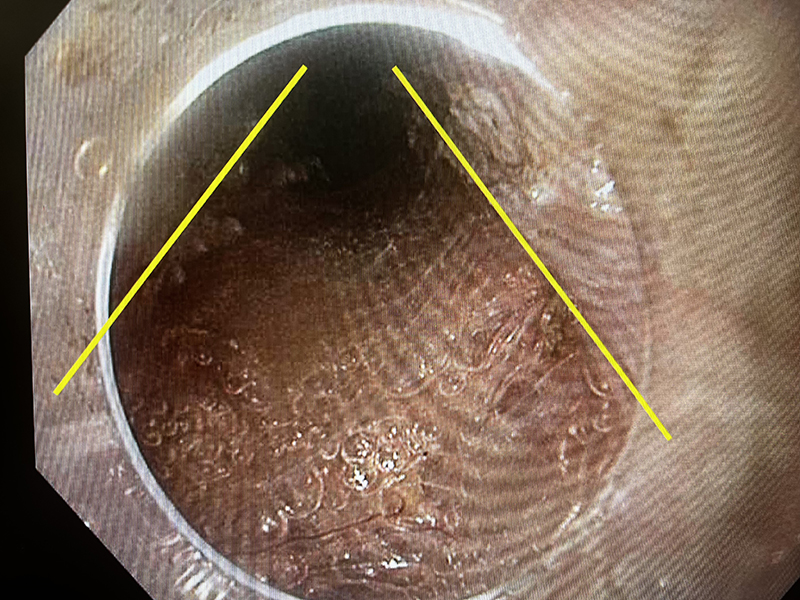

Myotomy

The full thickness myotomy exposed the mediastinum

Open EGJ s/p POEM

The oesphago-gastric junction has been successfully opened